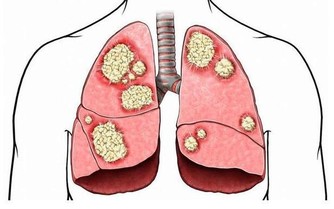

原來Josef是因為最近出現背痛、呼吸不順的症狀,才趕快赴往醫院檢查,起初他以為是肥胖因素導致身體出狀況,不過到院檢查後卻發現是肚子裡長著一顆腫瘤,大到已經擠壓到附近的器官:腎臟、肝臟與肺部,為求保命在醫生的建議下立即動手術移除腫瘤。